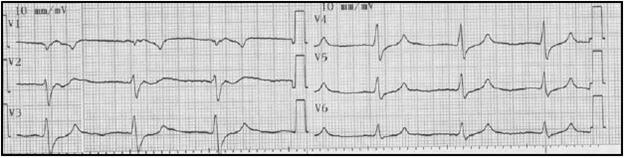

A su ingreso con tensión arterial en 90/60, frecuencia cardiaca: 50 por minuto, frecuencia respiratoria 14 por minuto y afebril. Se observa con signos de deshidratación grado II y estuporosa. Se toma glucometría en 95 mg/dL y electrocardiograma (Figura 1) con evidencia ausencia de onda P con R-R regular y ensanchamiento del complejo QRS (130 mseg), con intervalo QT corregido prolongado (460 mseg) y trastorno inespecífico de la repolarización. Se inicia manejo hídrico, oxigenoterapia, monitoreo electrocardiográfico y se toman paraclínicos. Se realiza electrocardiograma de control a los 10 minutos que muestra la presencia de una onda sinusoidal (Figura 2).

Ante la sospecha de hiperpotasemia, se inicia gluconato de calcio intravenoso a 10%, 10 cc cada 10 minutos hasta reversión de la onda sinusoidal (Figura 3), en total requirió 40 cc. Se reciben niveles de potasio en 8.6 meq/L, creatinina en 10 mg/dL y nitrógeno ureico en 110 mg/dL. Se complementa manejo farmacológico para hiperpotasemia y se interconsulta al servicio de nefrología para inicio de terapia de reemplazo renal urgente.